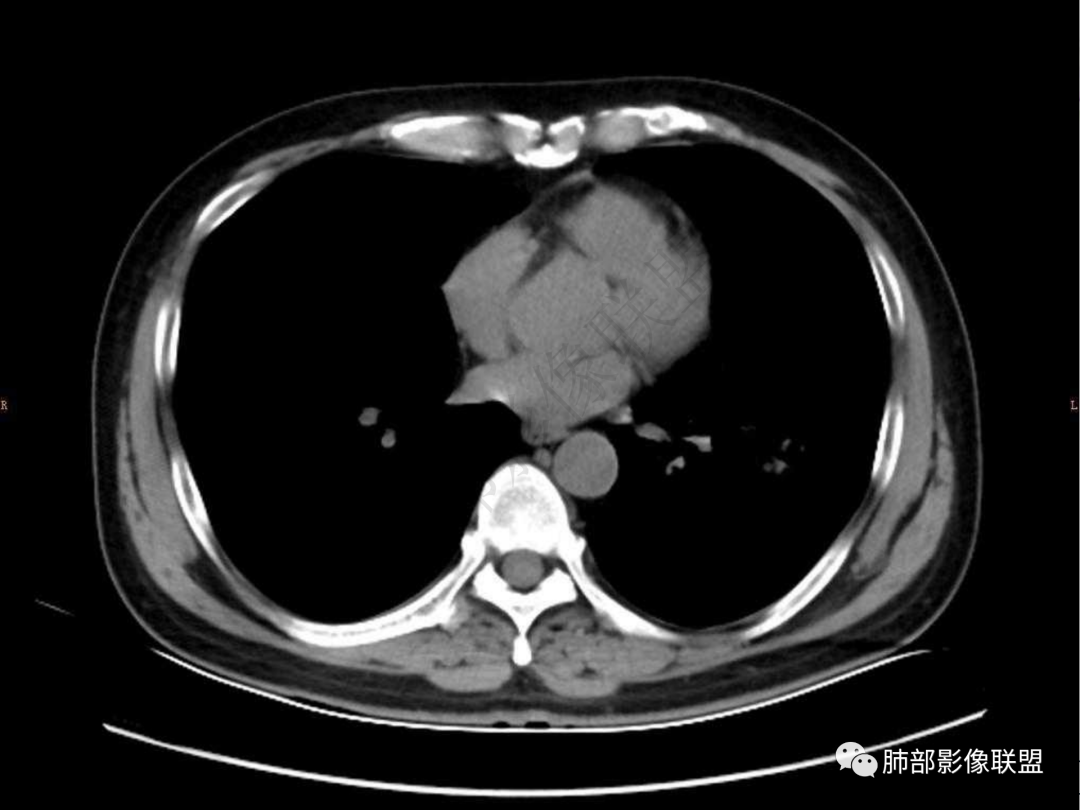

4.实性部分不均匀环形强化并显示一小范围低密度坏死区或空洞。较之肺窗,整体纵隔窗范围较小,提示病灶并不十分密实。抑或为不同时段图像。

1.病灶不够密实,没有典型分叶,收缩乏力等,支气管未见截断等,缺乏一般肿瘤性肿块特征。

六:增强扫描:

肺脓肿:环形强化,强化较显著。如出现明显囊壁样强化甚至边缘“憩室”样突出,高度支持肺脓肿。